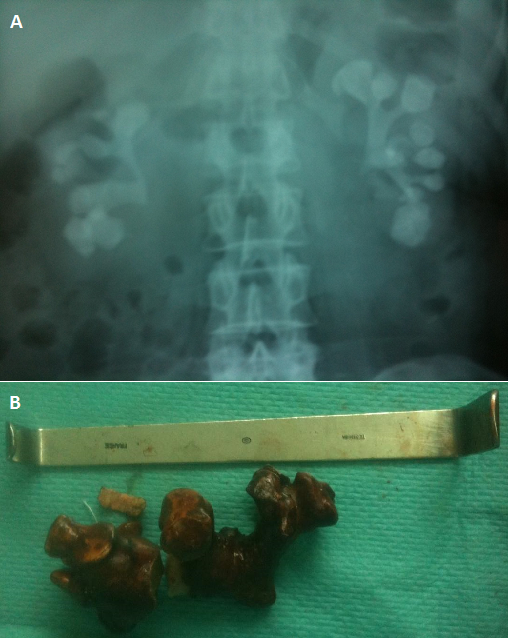

A middle aged women with bilateral staghorn complete calculi

A 50-year-old woman presented with a 2-years history of chronic flanc and hematuria. Plain abdominal radiography was performed showing bilateral complete staghorn calculi. Urinalysis and urine culture revealed a urinary infection by Proteus Morganii. Biologic investigations did not show any matabolic disorder. The urinary infection was treated by antibiotics and the stone by a combination of percutaneous nephrolitotomy and open surgery. The infrared spectrometry analysis found a calcium oxalate calculi. A Staghorn calculus is a large renal stone with irregular branches that can involve the renal pelvis and extend into calyces. Physiopatholgy of staghorn calculi is based on urinary infection. They are usually seen in the setting of infection with urease producing bacteria. They are composed of struvite (magnesium ammonium phosphate) but also, they can be composed of calcium oxalate. The majority of staghorn calculi are symptomatic: urinary infection, flanc pain, hematuria, urinary symptoms. The diagnosis can be performed by Plain abdominal radiography. Intravenous urography or CT scans are more helpful by showing the stone and delineating the pelvic calyceal anatomy. The treatment recommended of this type of renal stone is based on complete removal of all stone material after Sterilization of the urine with antimicrobial treatment. The elimination of all residual fragments can be obtained by the combinaison of different techniques: percutaneous nephrolitotomy, extracorporeal shockwave lithotripsy, retrograde ureteroscopic lithotripsy, open surgery. No treated, staghorn stone can cause septicemia, chronic renal insufficiency, destruction of kidney by infection and chronic calicial dilatation.